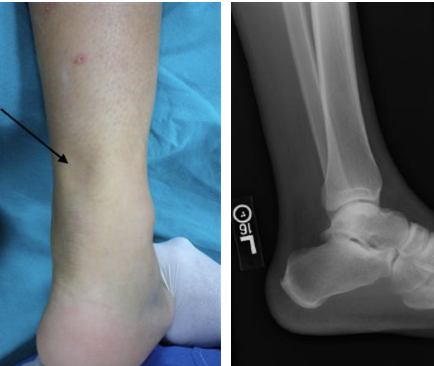

What is a March Fracture? [1]

**March fractures** are a **subtype** of **fatigue/stress fractures**. They occur due to repeated concentrated trauma to a normal bone, **classically the 2nd metatarsal of the foot** but can occur in other weight-bearing bones of the lower limb and pelvis.

How would you differentiate calcaneus stress fracture from plantar fasciitis? [1]

PF pain is worse with initial activity, then relieved Stress fracture pain will be worse with activity